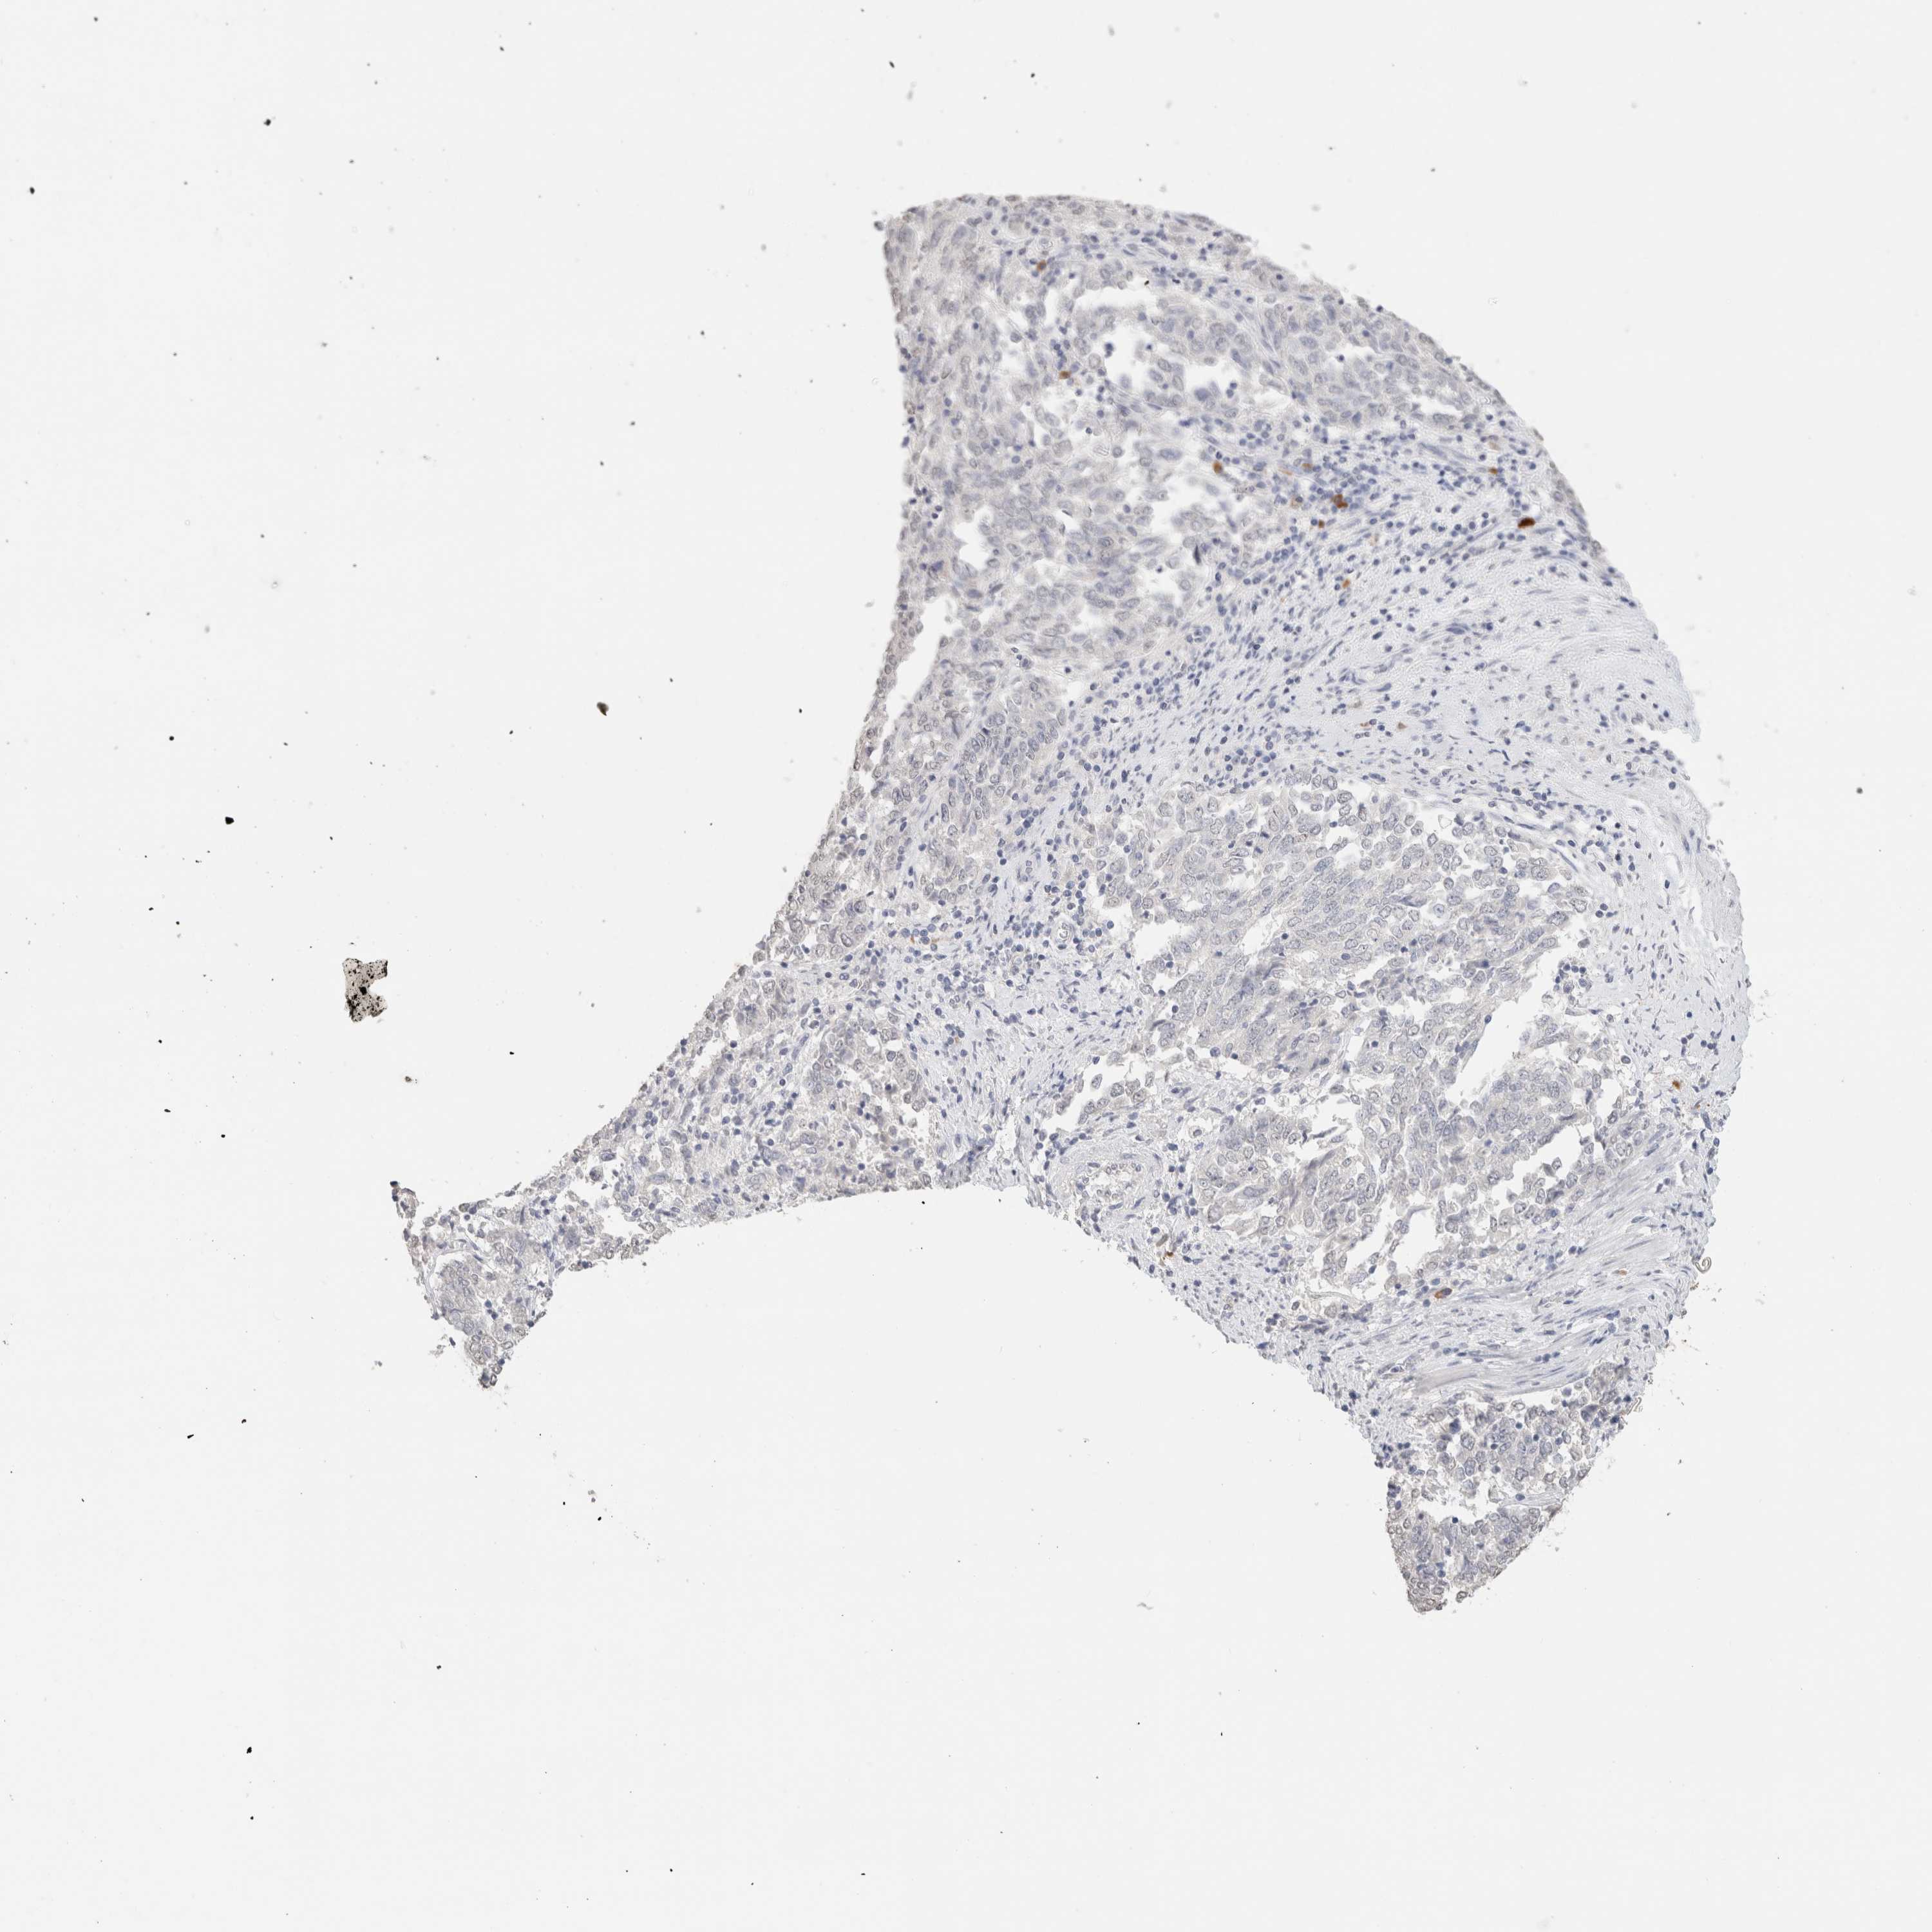

ENDOMETRIAL CANCER - Protein expressioni

A mouse-over function shows sample information and annotation data. Click on an image to view it in a full screen mode. Samples can be filtered based on level of antibody staining by selecting one or several of the following categories: high, medium, low and not detected. The assay and annotation is described here.

Note that samples used for immunohistochemistry by the Human Protein Atlas do not correspond to samples in the TCGA dataset.

Antibody stainingi

Antibody staining in the annotated cell types in the current human tissue is reported as not detected, low, medium, or high, based on conventional immunohistochemistry profiling in selected tissues. This score is based on the combination of the staining intensity and fraction of stained cells.

Each image is clickable and will lead to virtual microscopy that enables deeper exploration of all samples and also displays staining intensity scores, fraction scores and subcellular localization as well as patient and tissue information for each sample.

Antibody HPA050092

Antibody CAB025368

Staining

High

Medium

Low

Not detected

Intensity

Strong

Moderate

Weak

Negative

Quantity

>75%

75%-25%

<25%

None

Location

Nuclear

Cytoplasmic/membranous

Cytoplasmic/membranous,nuclear

Adenocarcinoma, NOS

Carcinoma, NOS

Adenocarcinoma, metastatic, NOS